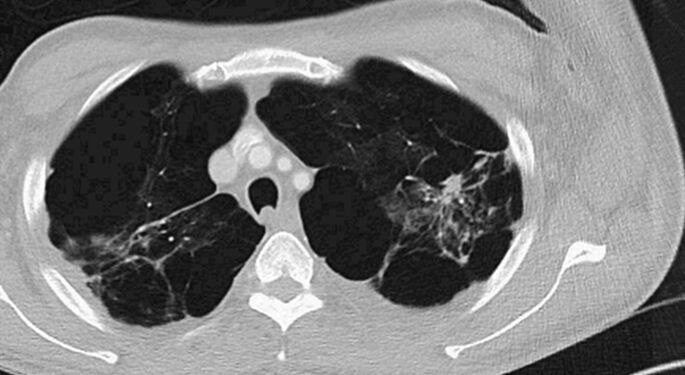

Pulmonary Fibrosis-ILD

Helping our patients get relief from this inflammatory respiratory disease

Lung Nodule-Lung Cancer

Providing life-saving early detection and care for lung nodules and lung cancer